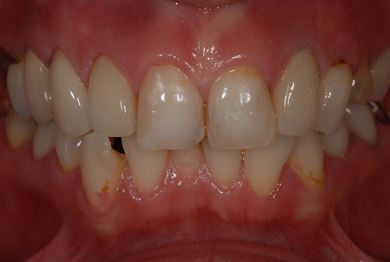

| 性別/年齢 | 女性 / 34歳 | ||||||||||||||||||||||||||||||||

| 主訴 | 現在痛みはなく、前歯の汚れを治したい。奥歯はブリッジを考えている。審美を考えているが、今治療をしたいというよりは、セラミックなど詳しいことがわからないので、計画や説明を伺いたい。 | ||||||||||||||||||||||||||||||||

| 治療方針 | 上前歯部分、セラミック治療にて審美的回復を行う。 | ||||||||||||||||||||||||||||||||

| 治療内容 | オールセラミッククラウン3本(オールセラミック用土台3本)、メタルボンドセラミッククラウン1本 | ||||||||||||||||||||||||||||||||

| 総治療費 | 562,800円 | ||||||||||||||||||||||||||||||||

| 治療期間 | 8ヶ月 |